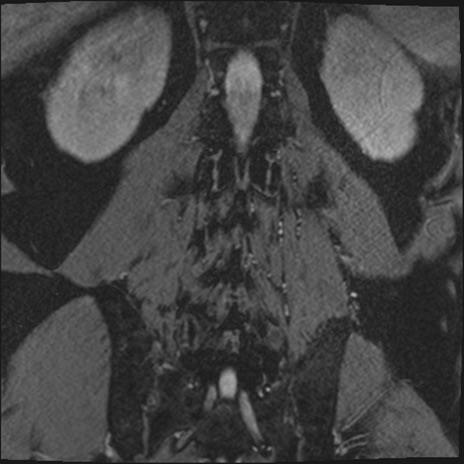

【整形】TIPS症例2 腰椎MRI 3D(冠状断像)

【症例】70歳代男性

【主訴】左下肢痛

【現病歴】2週間前くらいから腰痛、左下肢痛あり。左臀部から大腿、下腿外側のしびれが常時ある。歩行とともに同部位の痛みあり。

【身体所見】Lasegue70-/60+、Bragard-/±、PTR ±/±、ATR -/-、IP 5/5、TA 5/4、TS 5/5、EHL 右第1足趾なし/3、FHL 5/5、hypersthesia(-)、足背動脈触知良好

異常所見と診断は?